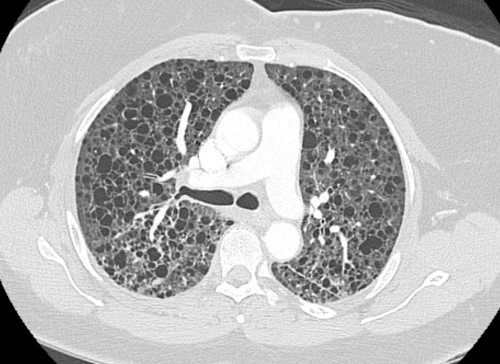

Age: 58

Sex: Female

Indication: Shortness of breath, cough

Sample ReportNumerous bilateral small pulmonary cysts. Recommend chest CT for further evaluation.

No evidence of pneumonia. No pleural effusion.